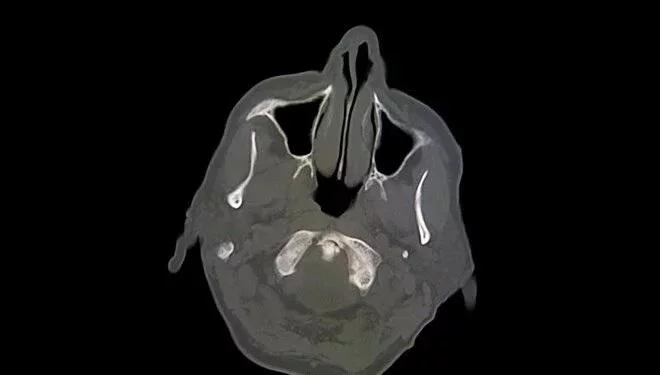

Beyin tomoqrafiyası zamanı məlum olub ki, kişinin beyninin yarısı yoxdur və onun kəllə sümüyündə nazik beyin toxuması və maye təbəqəsi var. Bu xəstəlik "Hidrosefali" adlanır. Koqnitiv psixoloq Aksel Kliremans qeyd edib ki, kişi normal həyat sürüb, ailəsi olub və işləyir. Şikayət etdiyi zaman alınan IQ testinin nəticəsi 84 olu, bu normal diapazondan bir qədər aşağıdır.

Həkimlər hesab edirlər ki, onun xəstəliyinə səbəb 30 il ərzində beynində yığılan maye olub və bu maye onun beyninin böyük hissəsinin məhv olmasına səbəb olub.

Digər tərəfdən xəstəlik körpə olanda aşkarlanıb və stent qoyulub. Lakin 14 yaşında ikən stent çıxarıldıqdan sonra beyninin çox hissəsi aşınmaya başlayıb. Keçmişdə şüurun beynin xüsusi sahələri ilə əlaqəli olduğu düşünülürdü, lakin bu cür həyat hekayələri şüurun yalnız xüsusi bir bölgə tərəfindən idarə olunmadığını iddia edən yeni nəzəriyyələrin ortaya çıxmasına səbəb oldu.